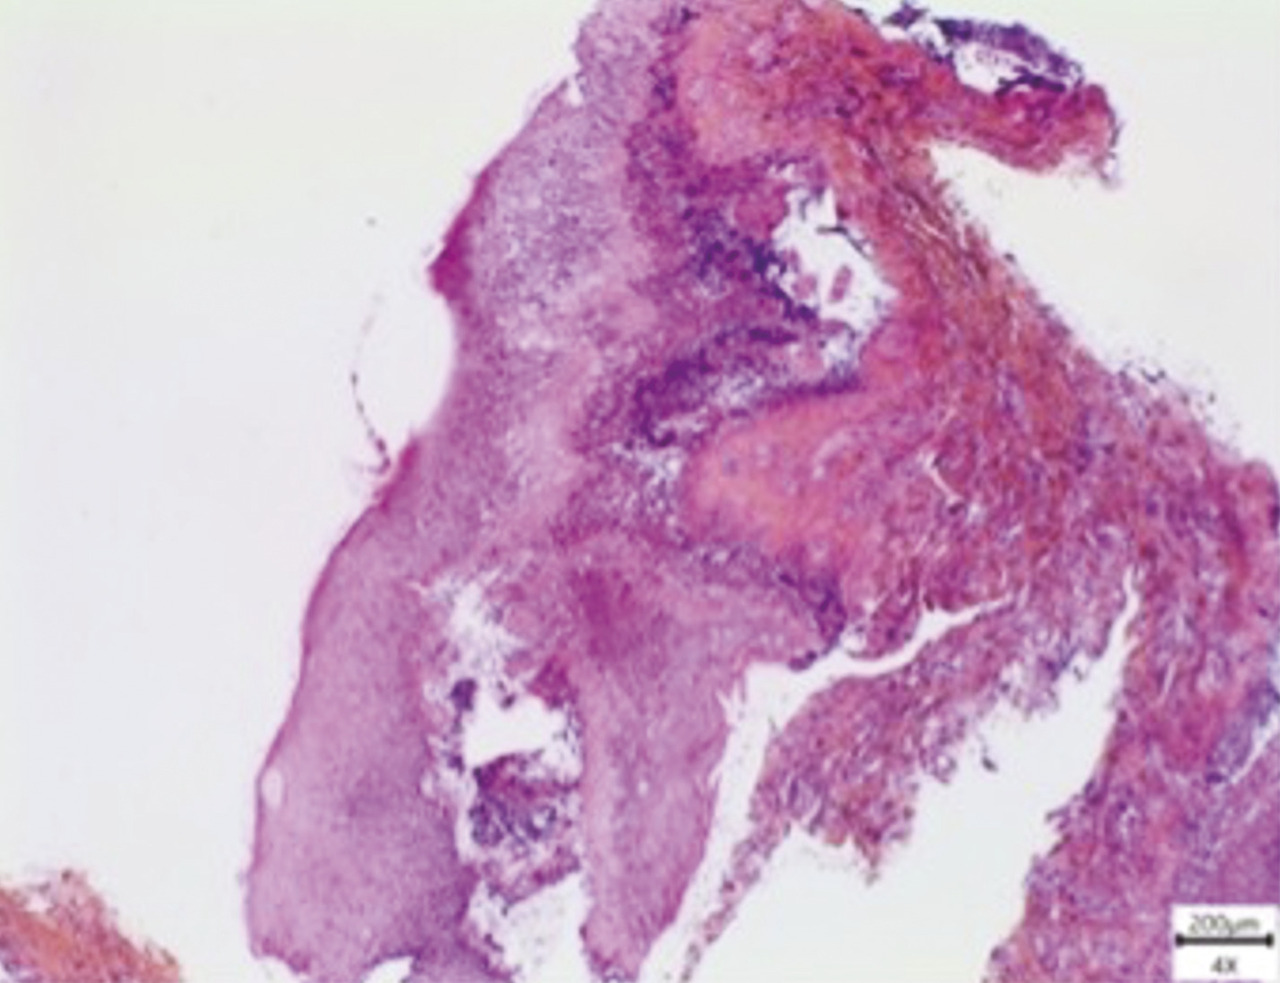

Une biopsie est effectuée, à cheval sur une lésion gingivale érosive et la muqueuse périlésionnelle. L’examen histologique révèle un toit bulleux composé d’épithélium, rempli de sérosités et d’un infiltrat inflammatoire abondant, principalement constitué de polynucléaires neutrophiles (fig. 3 ). Par la suite, une analyse en immunofluorescence directe met en évidence la présence de dépôts d’immunoglobulines G (IgG) et de fractions de complément (C3) le long de la membrane basale, cohérent avec le diagnostic de pemphigoïde bulleuse. Les dosages d’anticorps anti-BP180 et anti-BP230 sont négatifs.

Une biopsie est effectuée, à cheval sur une lésion gingivale érosive et la muqueuse périlésionnelle. L’examen histologique révèle un toit bulleux composé d’épithélium, rempli de sérosités et d’un infiltrat inflammatoire abondant, principalement constitué de polynucléaires neutrophiles (